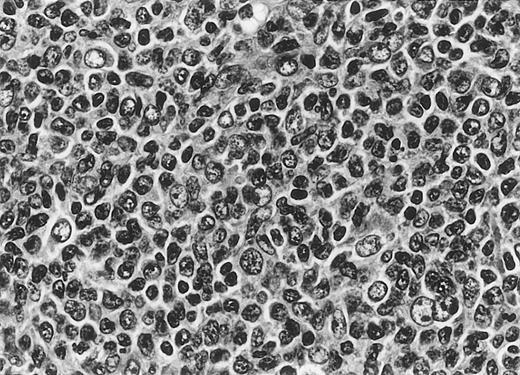

All cases of follicular lymphoma were classified as grade 2 according to the REAL classification. Histology showed bottom-heavy lymphoid infiltrates with prominent follicular pattern (Figures3 and 4). A well-formed mantle zone around most follicles was present only in 2 patients. In the other specimens the mantle zone was either reduced (11 patients) or nearly absent (2 patients) (Figure5). A clear-cut marginal zone was never observed. Tingible body macrophages within follicles were present only in 1 patient and were absent in the other 14 patients. Cytomorphology of follicles in all patients showed variable proportions of centrocytes (cleaved follicle center cells) and centroblasts (Figure6). The interfollicular areas revealed the presence of small lymphocytes and histiocytes admixed with a few larger cells and occasionally other inflammatory cells such as eosinophils and plasma cells.

Cytomorphology.

Centroblasts and centrocytes evident within a follicle (patient 3).